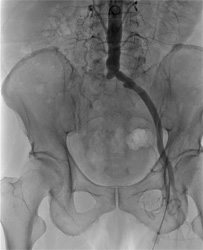

下肢動脈血管形成術

治療前   治療後

従来、放射線診断に用いられていた血管造影はCTやMRIの発展にともない、現在では主として治療目的のために行われています。この手法はIVR(インターベンショナル・ラジオロジー)と呼ばれています。

当院の血管造影室には、全身用にAlluraXperFD20、心臓血管造影用にはAlluraXperFD10/10(いずれもフィリップス社製)が導入され、フルデジタル化により再現性の高いデータを迅速に参照できるようになり、より精度の高い検査と治療を行っています。